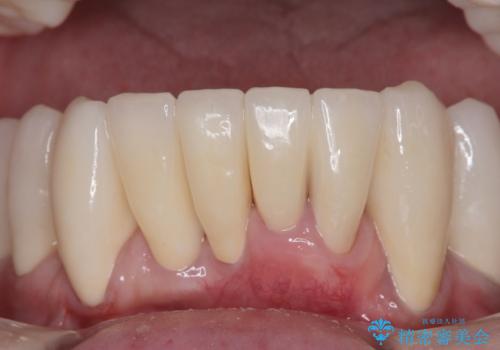

歯周病でグラグラの歯 矯正治療と歯周外科を併用した総合歯科治療

診察を行ったところ、重度歯周病の状態の上に上下の歯列が著しい叢生という状態でした。

上顎口蓋からの堅い歯肉を移植する角化歯肉移植術を行いたかったのですが、体調不良から実施しなかったため、最終補綴物であるオールセラミッククラウンを装着した後に、知覚過敏や境目が見てしまうといった問題が一部で発生いたしました。

最終的には痛みや違和感のない状態にて治療を終えることができました。